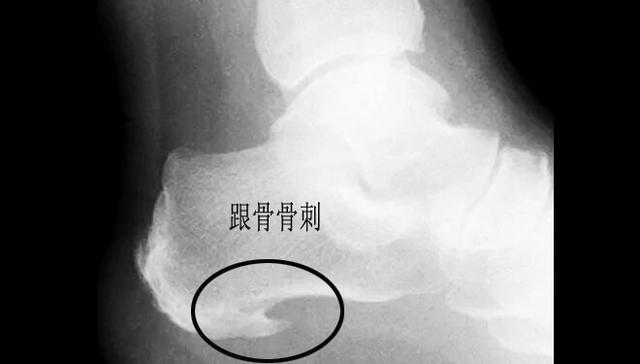

跟骨骨刺导致的跟痛

据数据统计,诱发足跟疼痛的诸多因素当中,跟骨骨刺占其中的15%,但是谢医生本人对这个几率存疑,因为这个几率太高了,临床上太多的患者足跟疼痛特别严重,但是并没有任何的跟骨骨刺。很多体检发现有巨大跟骨骨刺的患者追问病史反而没有丝毫症状

谢医生认为这些骨刺究其原因,还是因为足底筋膜受到了刺激,在于跟骨连接的部位出现了撕裂、出血,有一些患者在这个部位出现了钙化,最终导致了骨刺的形成

跟骨骨刺的治疗

无论是否是骨刺诱发的足跟下方的疼痛,只要存有症状,都可以参照足底筋膜炎的治疗方案,治疗建议以保守治疗为主。即使骨刺再大也不建议采取手术切除的办法治疗,很可能手术无效。

针对较大的跟骨骨刺暂时不建议采取冲击波治疗的办法,可能会导致骨刺骨折。